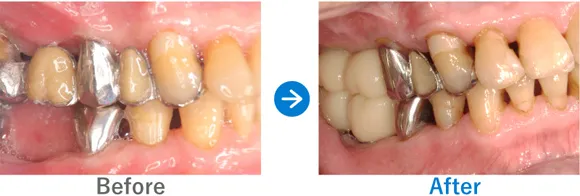

ほぼ虫歯な状態から、できるだけ歯を残した最小限のインプラントできれいな口元に

全顎ランパントカリエス(複数の歯に同時に虫歯が発生する状態)

インプラント4本:上顎2本、下顎2本、残せる歯はすべて補綴治療

4,917,000円(内訳:抜歯テルプラグ、GBR、根管治療、インプラント4本(ストローマン)、ガイド、全顎仮歯、補綴治療、セデーション、保証20年)

※当時の価格で現在とは異なる場合があります。

来院の背景

歯医者が苦手で、子供時代に歯科にかかったきりでした。ほとんどの歯に虫歯がある状態だったため、心配になったお父様が連れてこられました。

治療結果

まだお若いため、残せる歯はできるだけ残したうえで補綴治療(クラウンやブリッジなどによる治療)を行い、どうしても抜歯が必要な歯4本のみインプラントを行う方針で治療を進めました。

治療後は、見た目が整ったことはもちろん、しっかり噛めるようになったと喜んでいらっしゃいました。歯磨きが苦手とのことなので、定期メンテナンスでのアフターフォローも大切です。